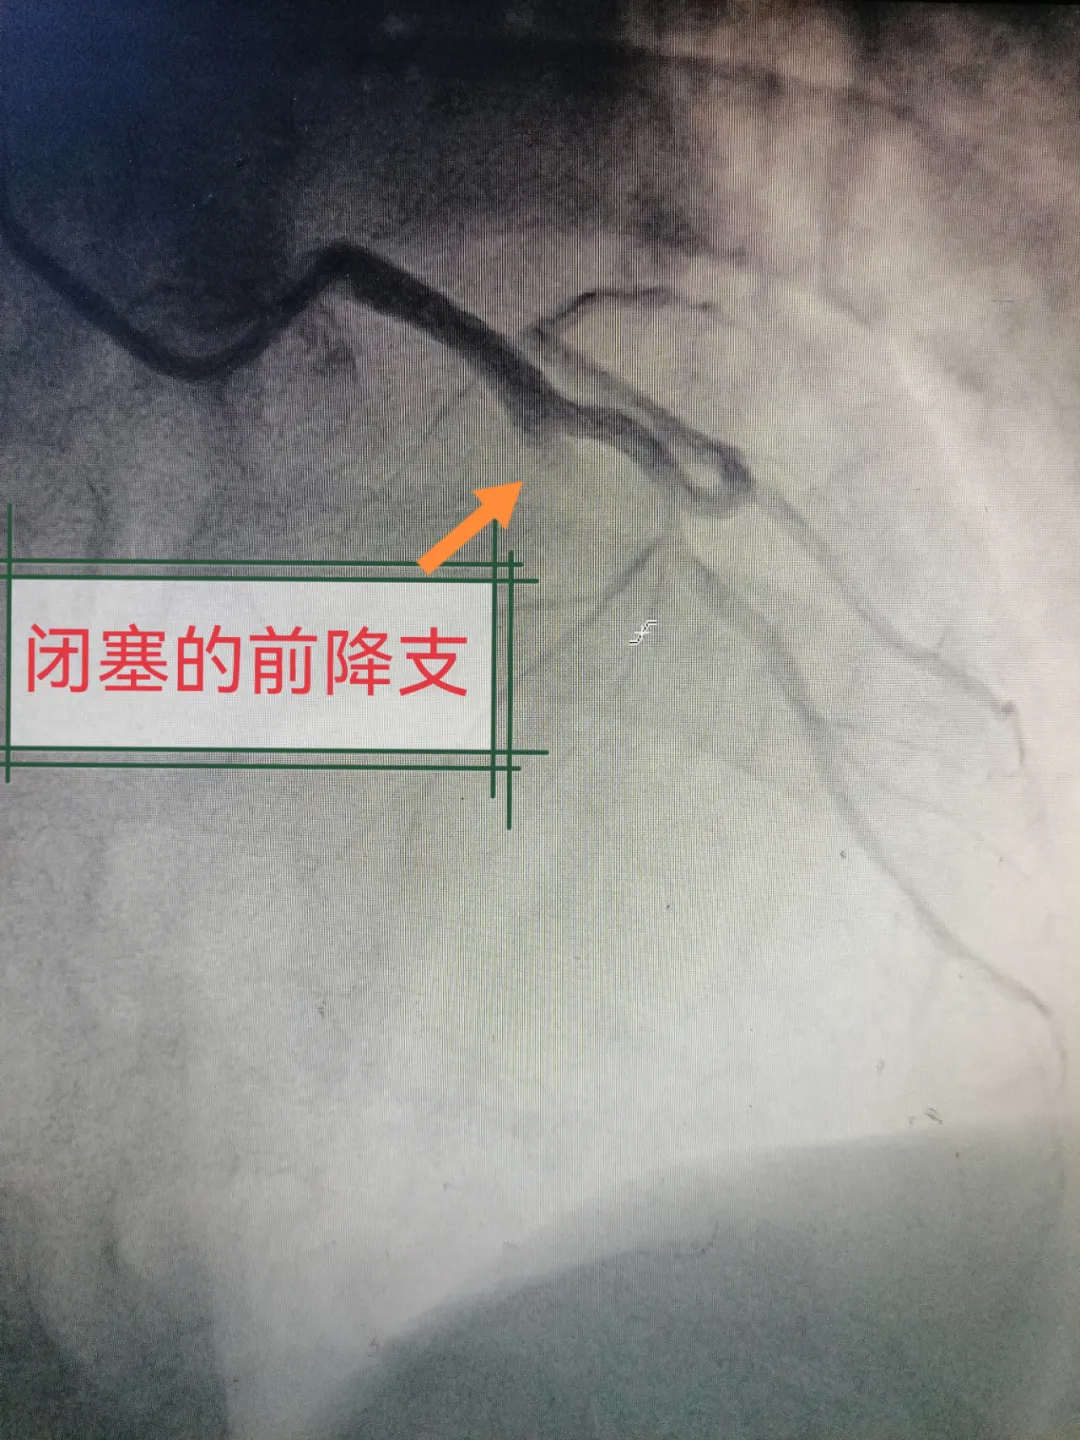

“立即启动导管室!”随着指令下达,我院绿色通道全面开启。介入团队迅速开展急诊PCI(经皮冠状动脉介入治疗),成功开通堵塞血管。从患者入院到血管开通(DtoB时间)仅用42分钟,医护人员凭借高效的急诊介入手术,成功将梁师傅从死亡线上拉了回来。

(△心脏闭塞血管及开通后血管图像)

尽管梁师傅顺利获救,但他心脏的部分心肌已坏死,留下了永久性损伤。我院心内科李南杰医生告知他:“你是幸运的,你的果断决策与我们的快速响应,共同挽救了你的生命。” 梁师傅长期吸烟、血脂偏高,且4兄弟中有3人曾因心脏问题植入支架的家族史,这些未被及时纠正的危险因素,正是此次心梗发作的关键诱因。